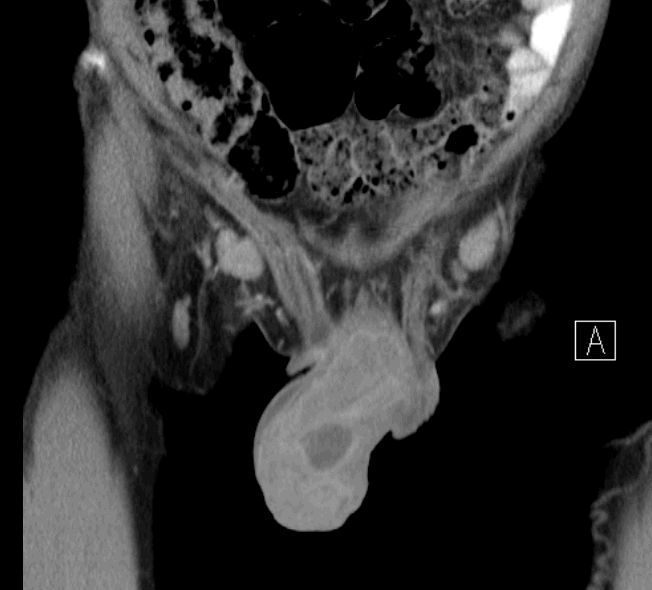

paraaortale Metastasen

Ausgedehnte Lymphnotenmetastasen paraaortal, paracaval und mesenterial